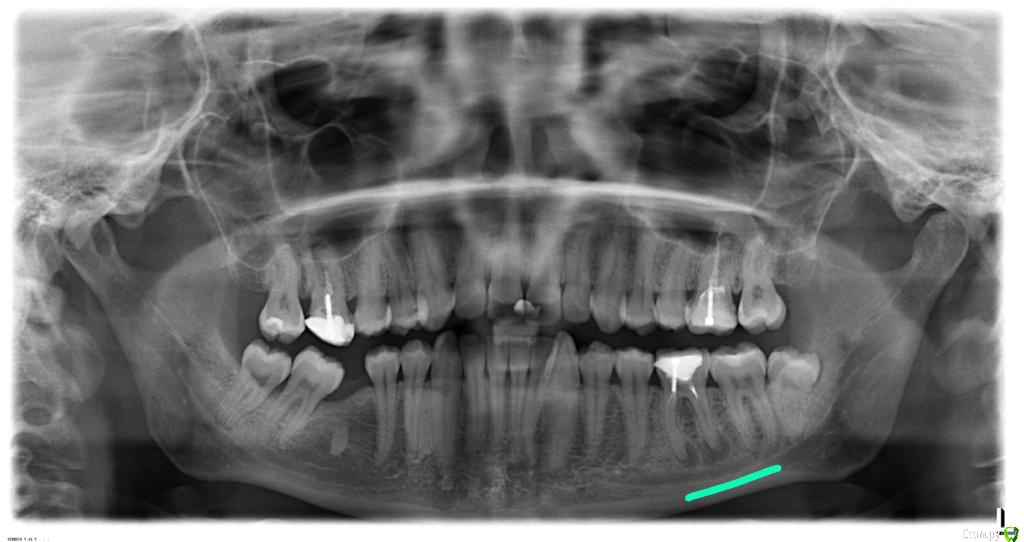

Mari1121 Опубликовано 18 августа, 2020 Поделиться Опубликовано 18 августа, 2020 (изменено) Добрый день, уважаемые специалисты.Крайне нужно Ваше мнение по проблемному зубу: требуется ли его удаление или возможно сохранить зуб, пролечив его?Болевые ощущения возникают во время приема пищи, отдает как раз где-то в десне. Боль непостоянна и не сильна.Снимок прилагаю. Зуб 6 справа (подчеркнула зеленым).Заранее спасибо! Изменено 18 августа, 2020 пользователем Mari1121 Ссылка на комментарий

red_butler Опубликовано 18 августа, 2020 Поделиться Опубликовано 18 августа, 2020 если судить только по рентгену то нужно зуб пере лечить и протезировать 1 Ссылка на комментарий